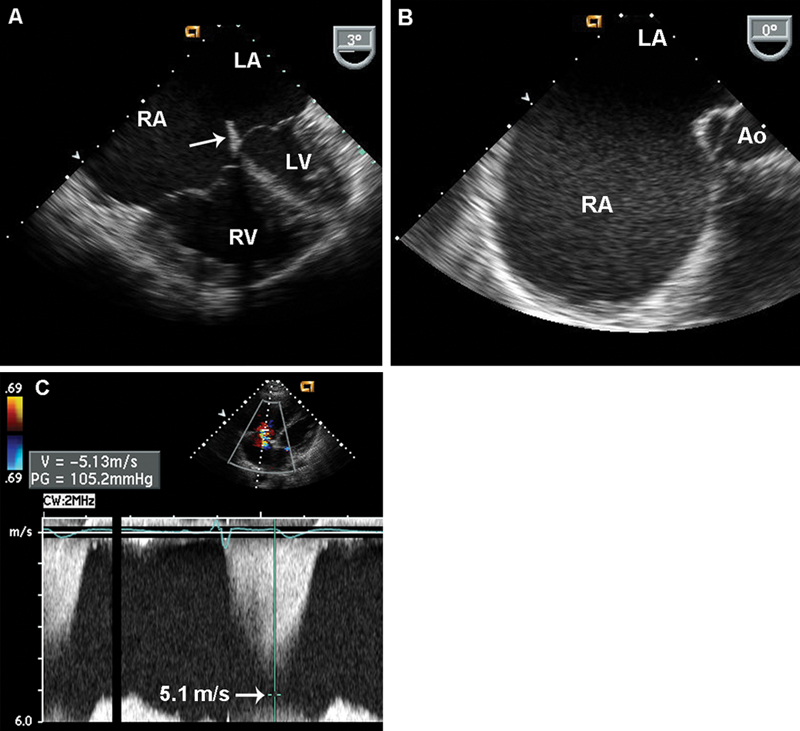

فحوصات تشخيصية لبعض امراض القلب والشرايين التاجية